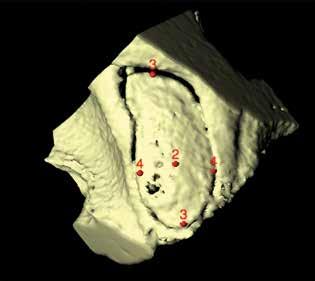

MicroCT and 3-D reconstruction. Images of the 20 temporal bones from the 10 selected crania were obtained on a microCT device (Inveon MicroCT; Siemens Healthineers; Erlangen, Germany). Since the gross physical sizes of the temporal bones exceeded the imaging aperture of the scanner, the specimens were physically reduced. The microCT images were then made with a pixel size of 20 × 20 μm, a slice thickness of 21.5 μm, and a resolution of 46.499 pixels/mm.

First, each stapes was cropped from the surrounding structures and ambient air by hand. Second, the “background noise” was subtracted. Third, the image stack was processed with the Isosurface algorithm of BoneJ, which converts the stack into a triangular surface model. The surface model was saved into a Standard Tessellation Language (STL) file format for dimensional analysis of the stapes structure. Fourth, the 3-D viewer was used to visualize the STL models. Reference points were marked directly on the 3-D models and recorded as x, y, and z coordinates.

Stapes measurements. The stapes height was calculated by measuring the distance between a point in the center of the top of the capitulum and a point in the center of the stapes footplate on the medial (vestibular) surface (figure 1). The footplate’s length was calculated by measuring the distance between points on both ends of the long axis of the footplate annulus. The footplate’s width was calculated by measuring points on both ends of the short and long axes of the footplate annulus.

After we created the models in BoneJ, we identified each landmark in 3-D space (x, y, and z) with the point tool. For measurements of the footplate length, we used the landmarks that represented the farthest point on the “big toe” side of the footplate and the farthest point at the “heel.” For footplate width, we determined the widest diameter perpendicular to the footplate length. Footplate dimensions were thus determined in a manner analogous to a shoe salesman measuring a foot (figure 2). Each measurement was performed twice, independently. Calculations and statistics. Distance measurements were calculated according to the Pythagorean theorem in three dimensions. Only if associations were suggested on scatterplot graphs were nonparametric Spearman correlations calculated. No correction for multiple comparisons was done.

Figure 1. MicroCT shows a right stapes viewed from a surgeon’s perspective, laterally onto the superstructure. Note the footplate’s socked-foot appearance, with the big toe anterorinferior. The red circle (1) indicates the center of the top of the capitulum.

Figure 2. MicroCT demonstrates a right footplate viewed onto the vestibular (medial) surface. The red circles denote the center of the footplate (2), the limits of its length (3), and the limits of its width (4) perpendicular to the length.